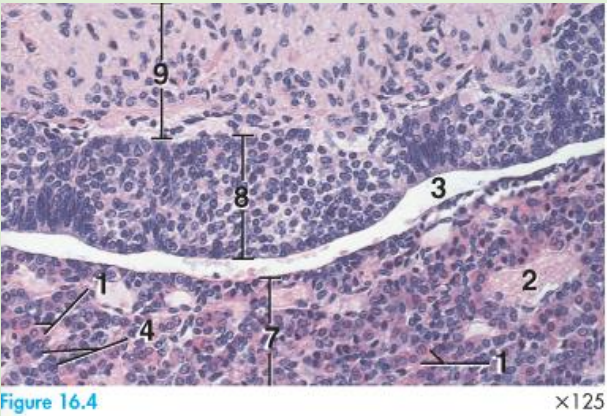

adenohypophysis - pars intermedia

Closely associated with pars nervosa

This part of the pituitary shows variation in size among species

Pars intermedia is a thin zone of basophilic cells (8)

Primary function is color change regulation

• Melanotrophs

• α-melanocyte stimulating hormone (α-MSH)

histology of neurohypophysis

9 pars nervosa

8 pars intermedia

3 cavity of Rathke's pouch

2 blood vessel

7 pars distalis